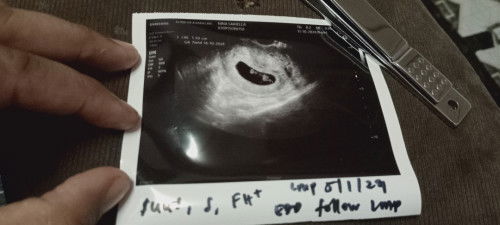

Salam semua, sy nak kongsi cerita dgn semua ibu² dlm ni, sy ni ibu anak 3 skrg ni, mengandung 5 kali 2x gugur, alhamdulillah di izinkan mengandung lg tahun ini kali ke6, sebelum ni sy gugur bln 12 tahun lepas, sy dpt tahu sy mengandung blk 15/2 dgn cek utp tapi samah² sy tak puas HATI sy beli yg mahal dpt la kptusan 3+ alhamdulillah syukur, Bermula la eps tak sbr nak p scan, oleh kena sy br lg ,tkt p scan tak napak,sy sbr smpi kandungan 8minggu+ br scan ,masa mula scan doc kata nanpak apa sbb angin dlm perut byk..doc mtk sy p kncing dan scan ikot bawah alhamdulillah nanpak dgn jelas dpt dgr FH++ lg bila doc ukur 7w6d doc kata sama Tarikh sy bg. doakan sy chat kuat smpi bersalin nanti aminn #doabaikbaik #8w5d